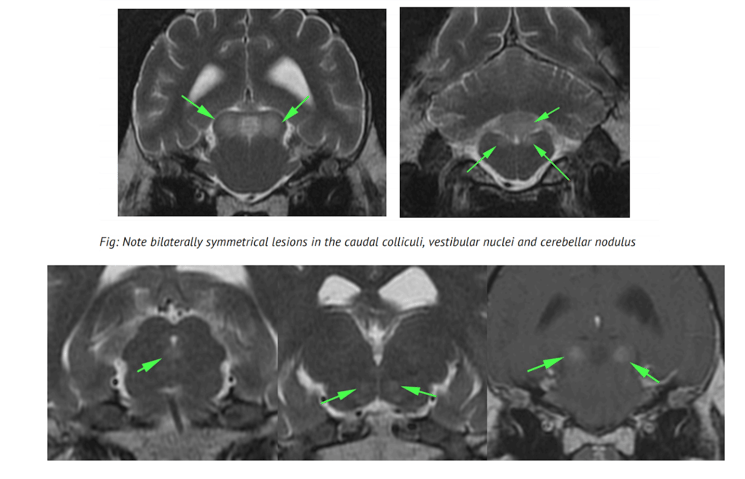

BRAIN: The brain is abnormal in appearance with bilaterally symmetrical focal areas of homogenous T2 hyper-intensity within grey matter involving the caudal colliculi, vestibular nuclei, red nuclei and ventromedially in the thalamus. There are similar lesions in the midline of the ventral para-aqueductal grey matter and the cerebellar nodulus. There is no mass effect or atrophy associated with the lesions.

No diffusion abnormalities are visible and there are no hemorrhages on the T2* GRE images. On the Tiw images the lesions are iso-mildly hypointense. The post-contrast images show dense, moderate enhancement of the caudal colliculi and vestibular nuclei lesions. No other abnormal enhancement is visible. The conformation of the brain is normal with no gyral or sulcal abnormalities. The rest of the grey and white matter are normal in signal intensity with no signal alterations. The ventricular system is normal in size and shape. There is a normal size and shape to the pituitary gland. No cranial nerve abnormalities are visible. The extra-cranial structures are normal.

Note lesions in the para-aquaductal grey matter and thalamus Enhancement of the caudal colliculi lesions

Conclusions: Thiamine deficiency

The presence of bilaterally symmetrical lesions is highly suggestive of a metabolic encephalopathy or toxicoses. The distribution of the lesions in this case is highly suggestive/pathognemonic for thiamine deficiency but definitive diagnosis would require measurement of thiamine levels. Enhancement of lesions in thiamine deficiency is seen sporadically and is not unusual.